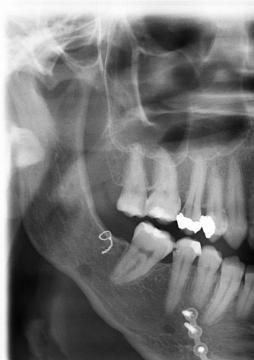

Zdravím, nedávno ma začal pobolievať zub v hornom rade na pravo. Bola to pulzujúca bolesť len sem tam no neskôr už tupá a neustála, pričom som už musela siahnuť po tabletke. Bola som u zubárky a tá mi len navŕtala a vložila dočasnú vložku. Lekárka je mladá preto ešte pre istotu prikladám fotku, či predsa sa tam nenachádza nález (zápal). Ďakujem

Dobrý den, na RTG nevypadá, že by se kolem kořene vyskytoval zánět (není zde projasnění). Pulzující bolest bývá i u kazu šířícího se do kořene. Myslím si, že vaše Zubarka postupovala správně.

Ešte dodám, že som po operácii sánky a brady.